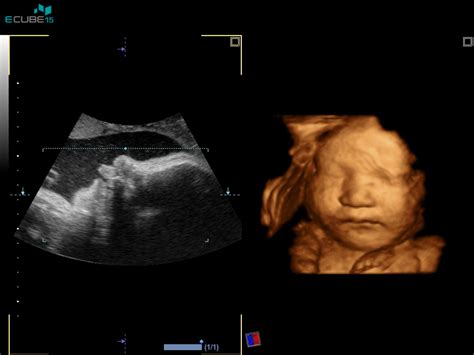

- Grozeči splav: Definiran kot krvavitev iz nožnice pred 22. tednom nosečnosti, ki jo lahko spremljajo blagi popadki. Z ultrazvočno preiskavo ugotovimo živ plod v maternici. Pogosto se opazi tudi manjša subhorionska krvavitev ali hematom.

- Snetljivo jajce ali anembrijska nosečnost: Ultrazvočna preiskava pokaže le gestacijsko vrečko brez odbojev ploda.

Molarna nosečnost (mehurčasta snet): Redko stanje, posledica nepravilne oploditve jajčne celice, ki jo odkrijemo z ultrazvočno preiskavo. V 3 do 10 % se lahko maligno spremeni v horiokarcinom.

Zaradi sodobne ultrazvočne in laboratorijske diagnostike ter dobre osveščenosti žensk večino nepravilnosti v zgodnji nosečnosti odkrijemo pred nastankom obilne krvavitve, ki bi lahko ogrozila življenje nosečnice. Verjetnost, da bo nosečnica, ki krvavi pred 20. tednom nosečnosti, potrebovala transfuzijo krvi, je majhna. Količina izgubljene krvi danes le redko preseže 500 ml.